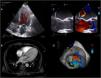

Figura 2.Relaciones del anillo mitral. Reconstrucciones con (A) ETE 3D, (B) CardioTC a nivel de base ventricular y (C) CardioTC a nivel de seno coronario.AP: arteria pulmonar; Cx: arteria circunfleja; OI: orejuela izquierda; SC: seno coronario; TD: trígono derecho y haz de His; TI: trígono izquierdo; TSVI: tracto de salida del ventrículo izquierdo; VAo: válvula aórtica; VM: válvula mitral; VP: válvula pulmonar.

Es importante destacar que en cirugía la posición de anillo mitral se reconoce bajo visión directa, pero en cardioTC y ecocardiografía se suele incluir la cortina mitroaórtica, ya que no hay un límite claro17.